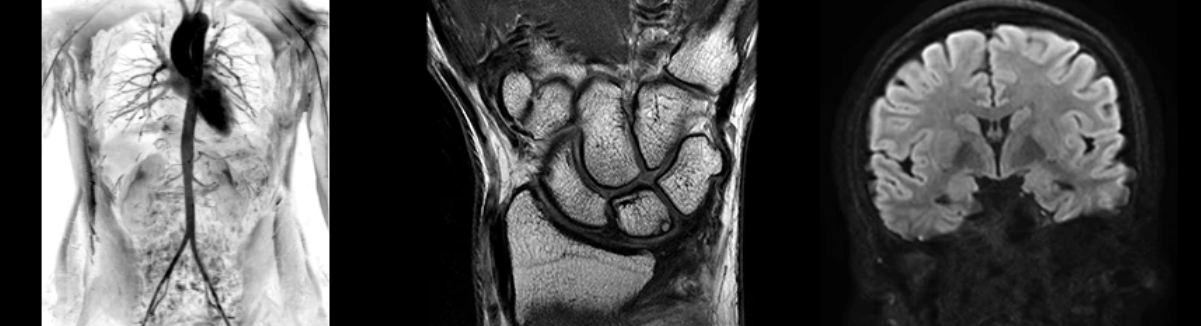

Магнитно-резонансный томограф GE SIGNA Premier

МРТ будущего — уже сегодня

МРТ SIGNA Premier — это результат четырехлетней совместной работы GE Healthcare и исследовательских центров над созданием и улучшением устройств для визуализации, которые смогли бы помочь врачам и ученым в выявлении и диагностике онкологических и неврологических заболеваний, в том числе и при легком повреждении мозга (mild Traumatic Brain Injury).

SIGNA Premier — система нового поколения для МРТ с широкой апертурой гентри от компания GE Healthcare и первый в области аппарат со 146-канальной РЧ-катушкой.

Производительность 60 см с апертурой 70 см

Signa Premier оснащается улучшенными протоколами HumanConnect (MultiShell DTI и высококачественным fMRI), получая изображение с большим разрешением, при этом не жертвуя комфортом пациента или размером апертуры гентри. Signa Premier сочетает в себе преимущества широкоапертурних системы со сверхвысокой производительностью, а в некоторых случаях превосходит другие высокопродуктивные системы с меньшими размерами апертуры, особенно для диффузионно взвешенных исследований.

Диффузное изображение еще никогда не было таким информативным

Как стандартный биомаркер в онкологии, диффузные изображения играют решающую роль в выявлении и стадии рака. Однако, из-за склонности некоторых анатомических областей в больших искажений, ограничивающих разрешение, действующий стандарт для диффузионной визуализации имеет свои ограничения. SIGNA Premier использует интеллектуальные количественные решения и расширенный пакет диффузии для автоматического обнаружения и исправления искажений, артефактов и движения. Результатом является совместная улучшенная регистрация с анатомической информацией, улучшенная визуализация структур в трудно изображаемых областях и более высокое разрешение без ограничений. Это достигается без какого-либо вмешательства пользователя, дополнительного времени сканирования или усложненного рабочего процесса.

Технология полной оцифровки изображения Total Digital Imaging (TDI)

Радиочастотная технология SIGNA Premier разработана для обеспечения большей клинической производительности и высокого качества изображения, особенно для приложений, требующих большого количества данных, на основе архитектуры Total Digital Imaging (TDI). 146 независимых каналов позволяют одновременно сочетать несколько поверхностных катушек со сверхвысоким количеством каналов для более быстрых ускорений и бескомпромиссной четкости изображения.

48-канальная катушка для головы

Компания GE Healthcare разработала 48-канальную катушку для головы, которая гарантирует феноменальную производительность почти для всех больных. Дизайн катушки учитывает 99,99% населения, включая пациентов со сверхбольшой головой и короткой шеей.

При этом сохраняется высокое отношение сигнал/шум (SNR) и отличное качество изображения. Кроме того, на сканере SIGNA Premier вы сможете выполнить быстрое сканирование мозга не более пяти минут.

- NeuroWorks

Представляет собой универсальное решение для визуализации анатомии головного мозга, позвоночника, сосудов и периферических нервов с четкой дифференциацией тканей.

- OrthoWorks

Программное решение OrthoWorks разработано для визуализации структур опорно-двигательного аппарата с прекрасным контрастированием тканей.

- BodyWorks

Используйте BodyWorks для визуализации абдоминальной и тазовой областей с учетом любых типов пациентов.

- OncoWorks

Включает клинические приложения для обработки и визуализации анатомических и морфологических данных, специфичных для каждого типа онкологических образований.

- CVWorks

Приложение для кардиовизуализации, с помощью которого вы сможете получить данные о морфологии, динамике кровотока, функции миокарда, а также информацию о структуре сосудов.